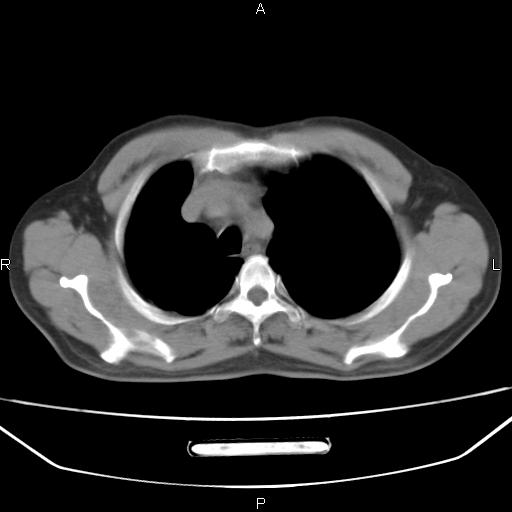

患者,男。50岁。近几日有咳嗽症状,无其他不适,既往病史无,考虑膈疝。请前辈们看看指导指导。

膈膨升,左下肺通气不良,膈肌好像还完整。

考虑左侧膈疝。

左侧膈疝。

符合隔膨升,膈肌较完整。